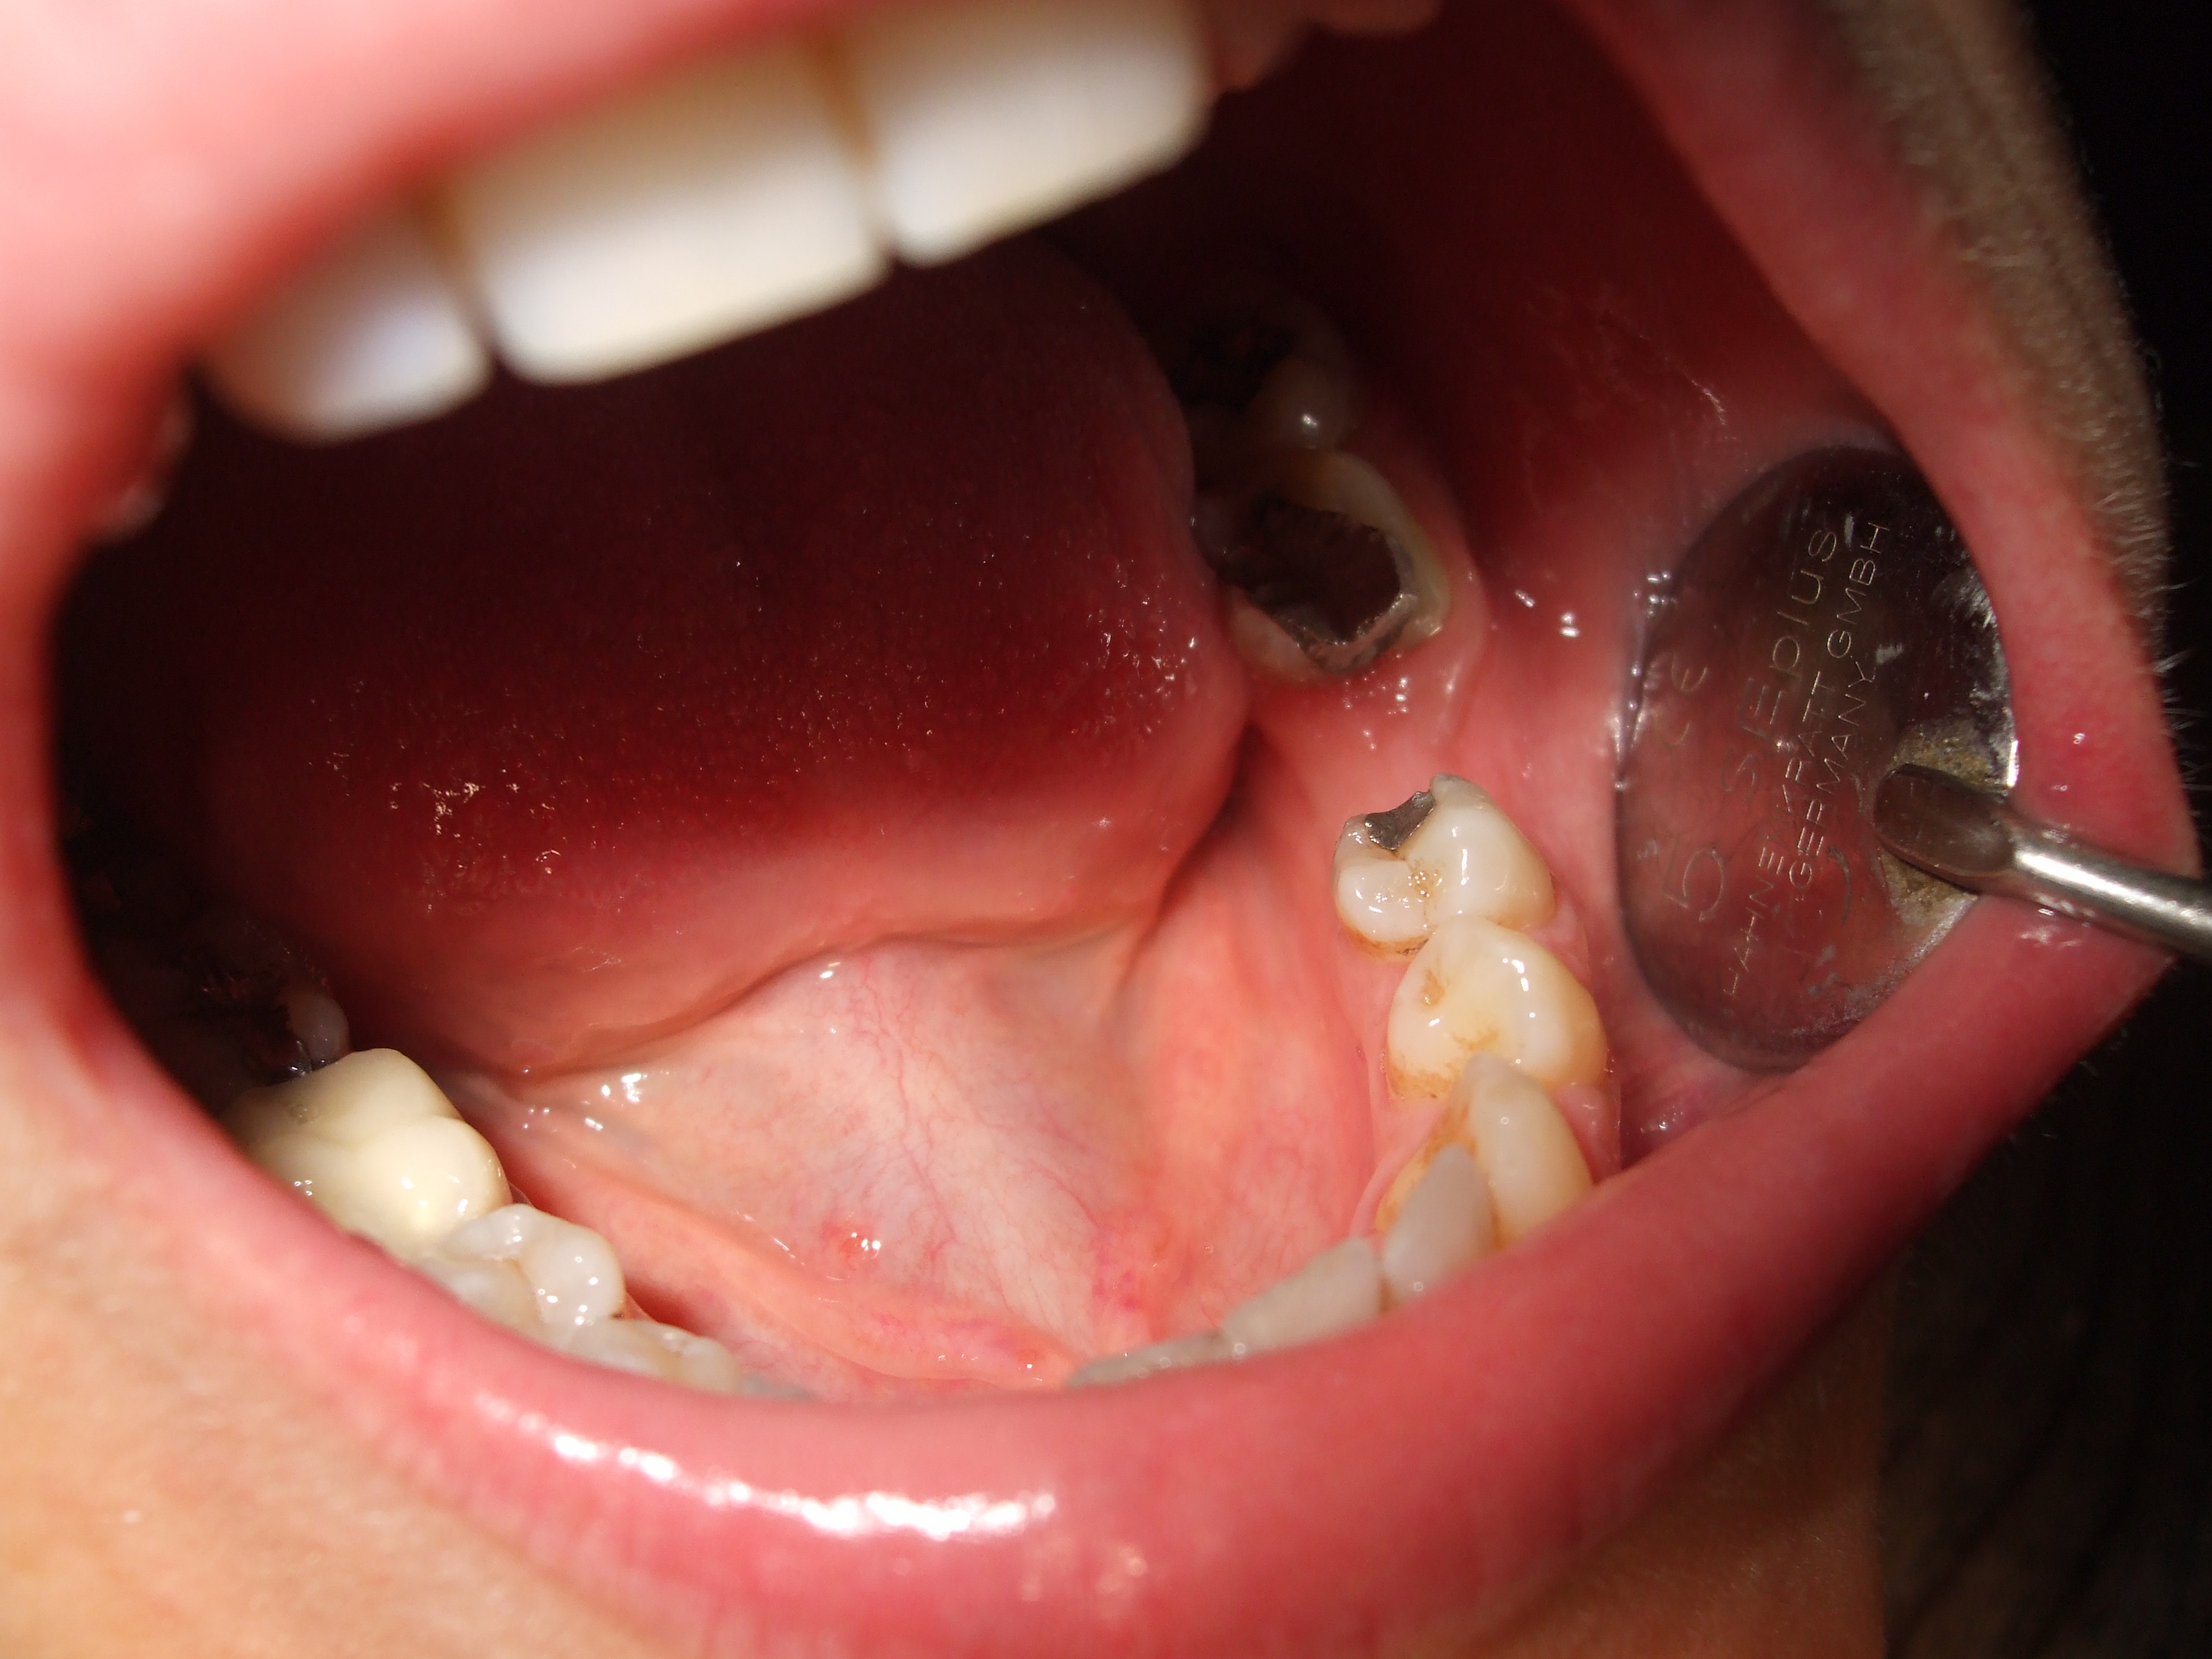

Ragazza di circa trenta anni con perdita del primo molare di destra inferiore(36) per carie destruente. E' stato inserito un impianto di diametro 4mm per 12mm di lunghezza utilizzando poi una vite di chiusura più alta transmucosa per evitare un secondo intervento chirurgico di scopertura dell'impianto su una gengiva già guarita.

Nel caso in questione si descrive un mono impianto con vite di chiusura trans-mucosa senza necessità di secondo intervento chirurgico di scopertura dell'impianto.